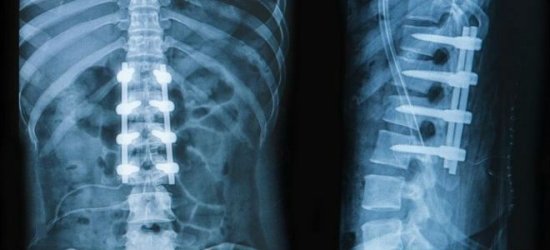

Грыжа позвоночника

Грыжа позвоночника – частая причина боли

Еще один источник болей в пояснице – наличие межпозвонковых грыж. При их ущемлении, сдавливании нервных корешков возникает довольно сильная, резкая боль, справиться с которой на начальных стадиях помогают стероидные и нестероидные противовоспалительные препараты.

Компьютерная томография является эффективным и высокоинформативным способом выявления различных структурных изменений в позвоночнике, вызванных травматизацией, инфекционным процессом, опухолевыми образованиями, остеопорозом и другими заболеваниями. В основе миелографии лежит применение контрастирующего вещества. Метод применяют при подозрении на стеноз позвоночного канала, грыжевых образованиях, опухолях и других патологических процессах в позвоночнике.